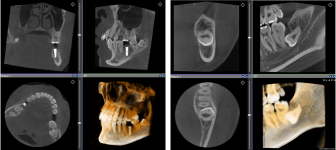

歯科用CT(3Dレントゲン)撮影

低被ばくで、広い範囲の撮影が可能なCT(3D撮影)機器です。デジタル方式ですので、被ばく量が従来のものと比べ各段に軽減されています。

3D撮影ができることにより、多角的な診断が可能となり、インプラント治療などにおける診断をはじめ、複雑な治療である親知らずの抜歯や根管治療を安全に、且つより正確に行うことが可能です。